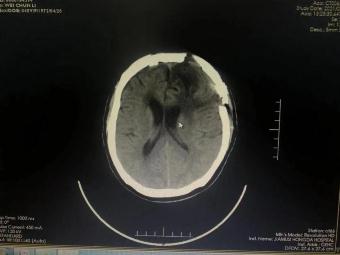

手術(shù)前 手術(shù)后

術(shù)前神經(jīng)外科與麻醉科、手術(shù)室、輸血科等科室反復(fù)認(rèn)真研究,制定了精細(xì)的手術(shù)方案和應(yīng)急預(yù)案。2月23日手術(shù)如期進(jìn)行并成功順利完成。術(shù)后第一日,患者神志清、言語明,對答問題流利切題;查體配合,右側(cè)肢體肌力明顯增強(qiáng),生命指征平穩(wěn)。術(shù)后在神經(jīng)外科護(hù)理團(tuán)隊的精心護(hù)理下,患者恢復(fù)良好,可正常離床活動,目前已經(jīng)康復(fù)出院。